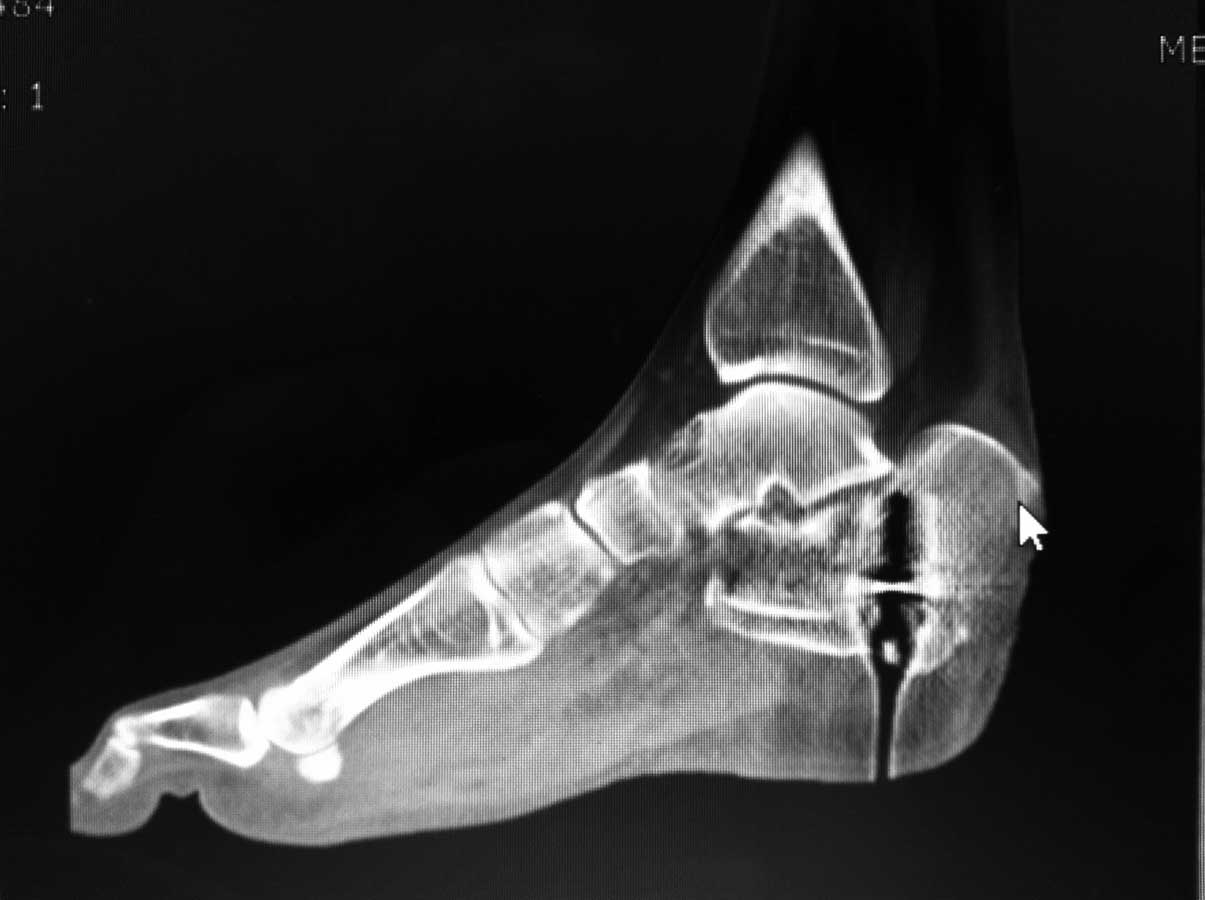

Re: Перелом пяточной кости - ваше мнение?

немного КТ